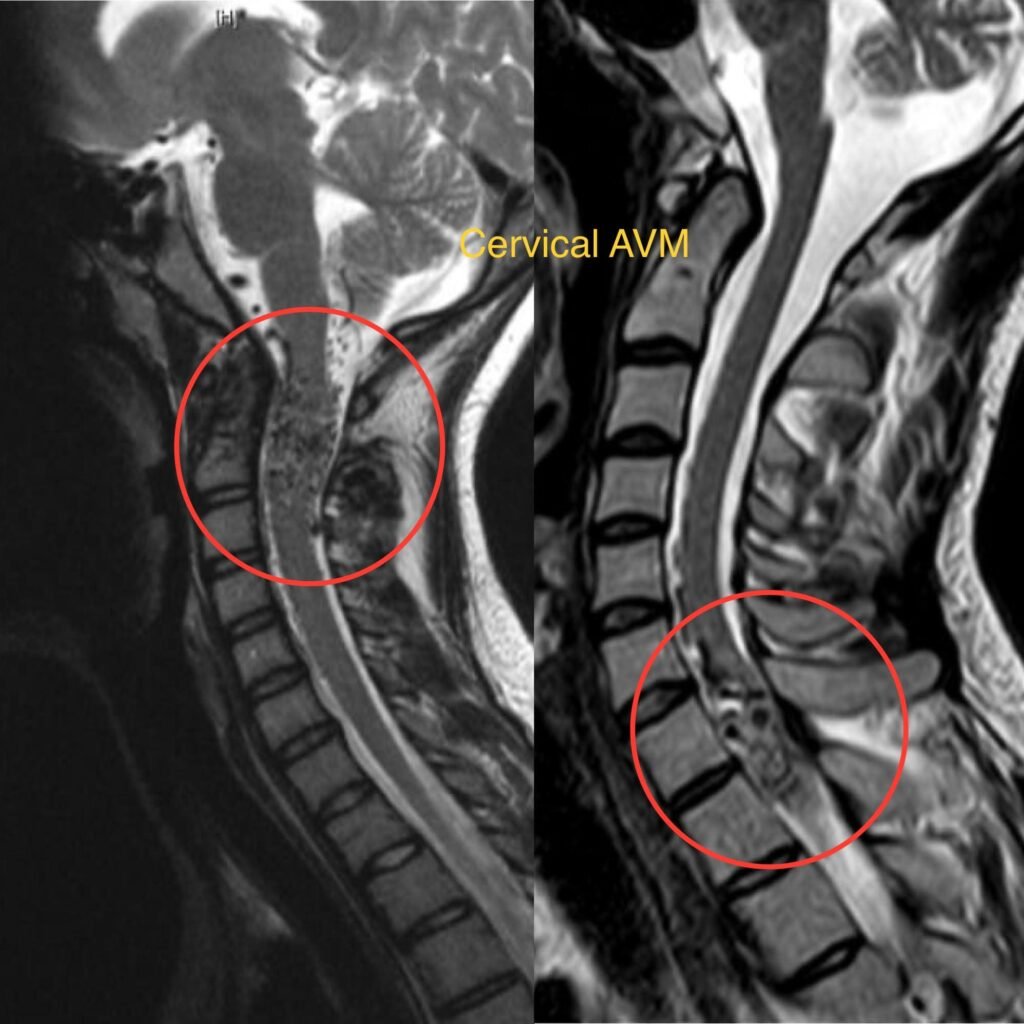

Spinal Arteriovenous Malformation (AVM)

Spinal Arteriovenous Malformation (AVM) is a rare vascular abnormality characterized by tangles of abnormal blood vessels in the spinal cord. These abnormal blood vessels disrupt normal blood flow, leading to various neurological symptoms.

• Diagnosis typically involves a thorough medical history, physical examination, and imaging studies such as MRI or angiography to visualize the abnormal blood vessels.